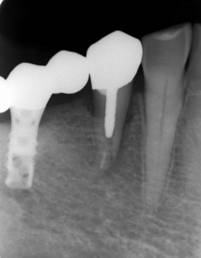

ストローマンインプラントとスプラインインプラント

術前

ストローマンインプラントとスプラインインプラントが隣り合わせに埋入されています.このころストローマンからスプラインに変えています。変えた理由は前歯部の審美性に優れていること、アバットメントの自由度があること、抜歯後すぐに埋入できるなどでした。

6年後。犬歯にコンポジット充填。第一大臼歯はメタルボンドになりました

8年後ほとんど変化がありません